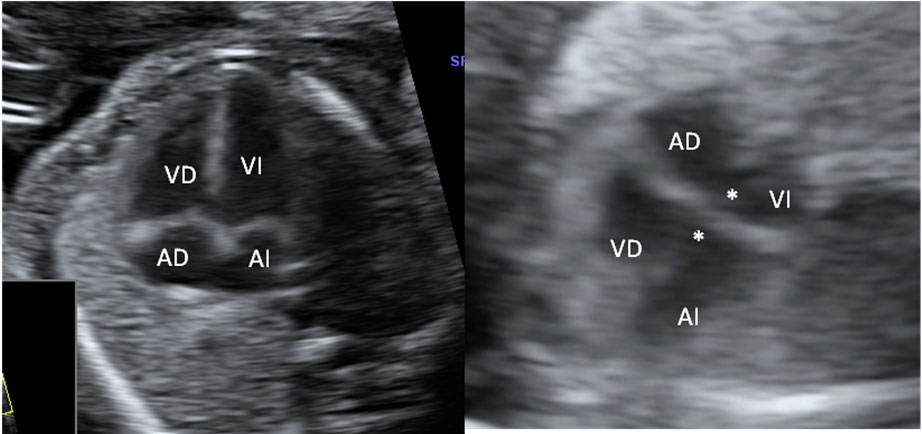

Corazón fetal en el que se aprecia una mancha brillante o foco ecogénito

La imagen de la flecha indica el foco ecogénito en el ventrículo izquierdo.